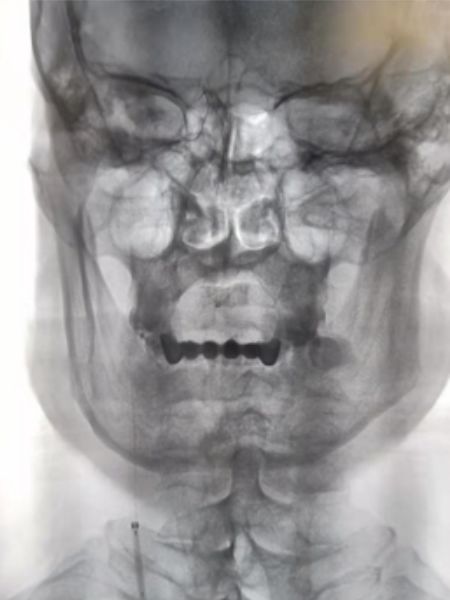

2019-06-07外院DSA:右侧颈内动脉闭塞(图2)。

图2